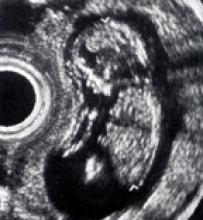

Physicians at Northwestern Memorial Hospital in Chicago were as stunned in 1979 by Godfrey Hounsfield’s exclamation as Hounsfield was at the computed tomography (CT) image. “My word, what is that?” asked the inventor of computed tomography, who later that year would receive the Nobel Peace Prize for his invention.